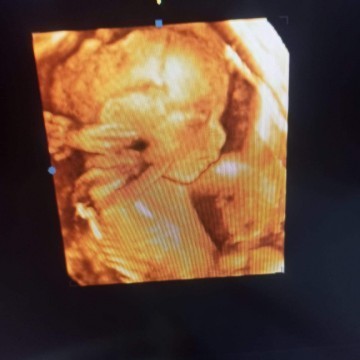

พึ่งซาววันนี้ค่ะ 21week คุณหมอใจดีให้เราดูแบบ4มิติด้วยค่ะ